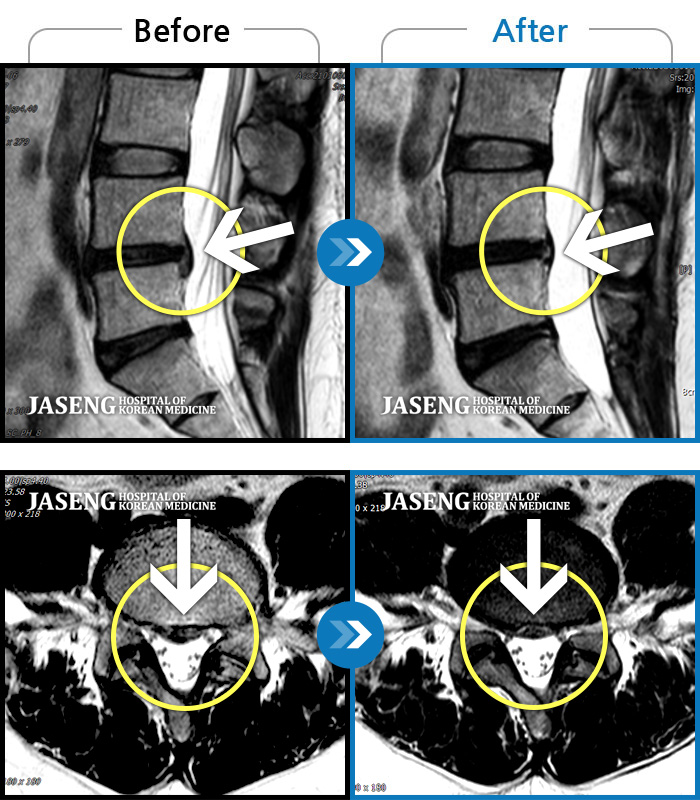

[뱸] 19.11.28~25.05.06

ȯںп Ǹ ǿ ԿǾ, ο ġ ۿ Ƿ ġḦ Ͻñ ٶϴ.